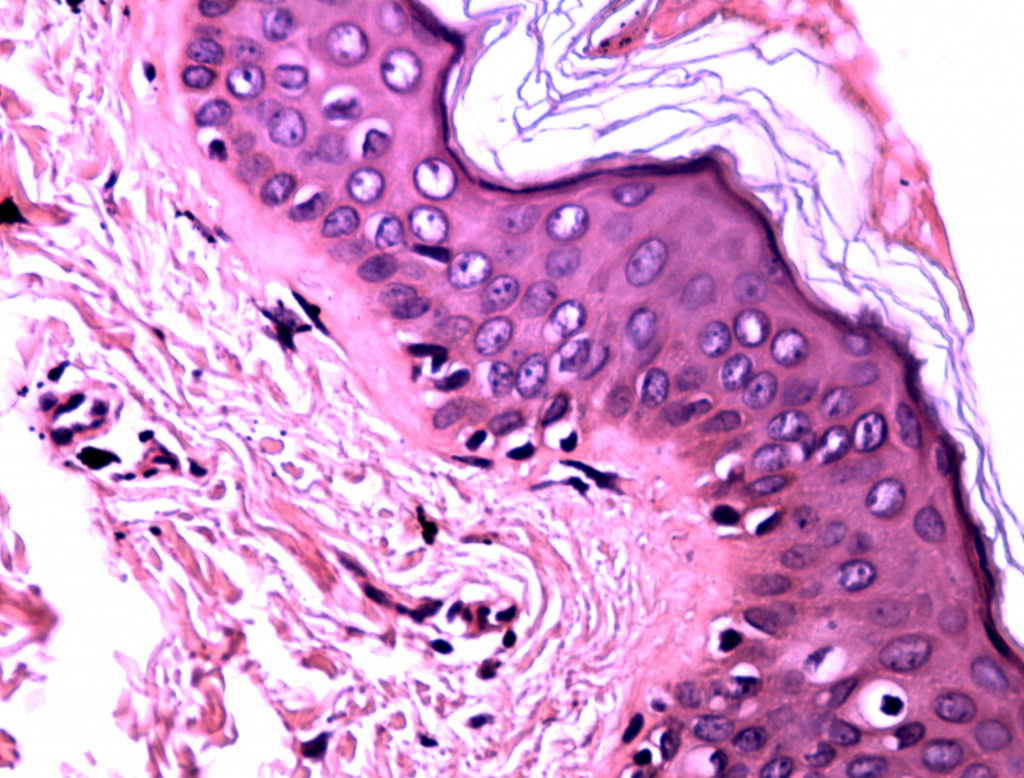

Уже после первой процедуры отмечается выравнивание цвета лица и увеличение тургора кожи (рис. 1-2). Процедуры переносятся очень комфортно, небольшая гиперемия в некоторых случаях держится до 30 минут. По результатам 3D-сканирования уменьшилась выраженность мелких морщин вокруг глаз уже через 6 дней после первой процедуры (рис. 1-6). Также проведено гистологическое исследование сразу после процедуры (рис. 7) (фрагмент «тонкой» кожи: единичными лейкоцитами в толще эпидермиса и на его поверхности, ядра клеток эпидермиса и их цитоплазма на данном участке набухшие, сосочки дермы несколько сглажены, рыхлая волокнистая соединительная ткань сосочкового слоя дермы отечна), на третий день (рис. 8) (отмечается уменьшение количества набухших ядер в эпидермисе, мелкоочаговое кровоизлияние в сетчатом слое дермы с перифокальной сосудистой реакцией и слабовыраженным отеком сетчатого слоя дермы) и спустя 20 дней после процедуры (рис. 9) (В представленном фрагменте кожи заметна умеренная пролиферация клеток эпидермиса и дермы. Отмечается уплотнение коллагеновых волокон сетчатой дермы. Патологических изменений в эпидермисе, дерме, придатках кожи не обнаружено). Также наблюдаются изменения показателей влажности, пигментации и эластичности кожи (рис. 10-11).

Гистология сразу после процедуры HELEO4

Рис. 7. Гистология сразу после процедуры HELEO4™